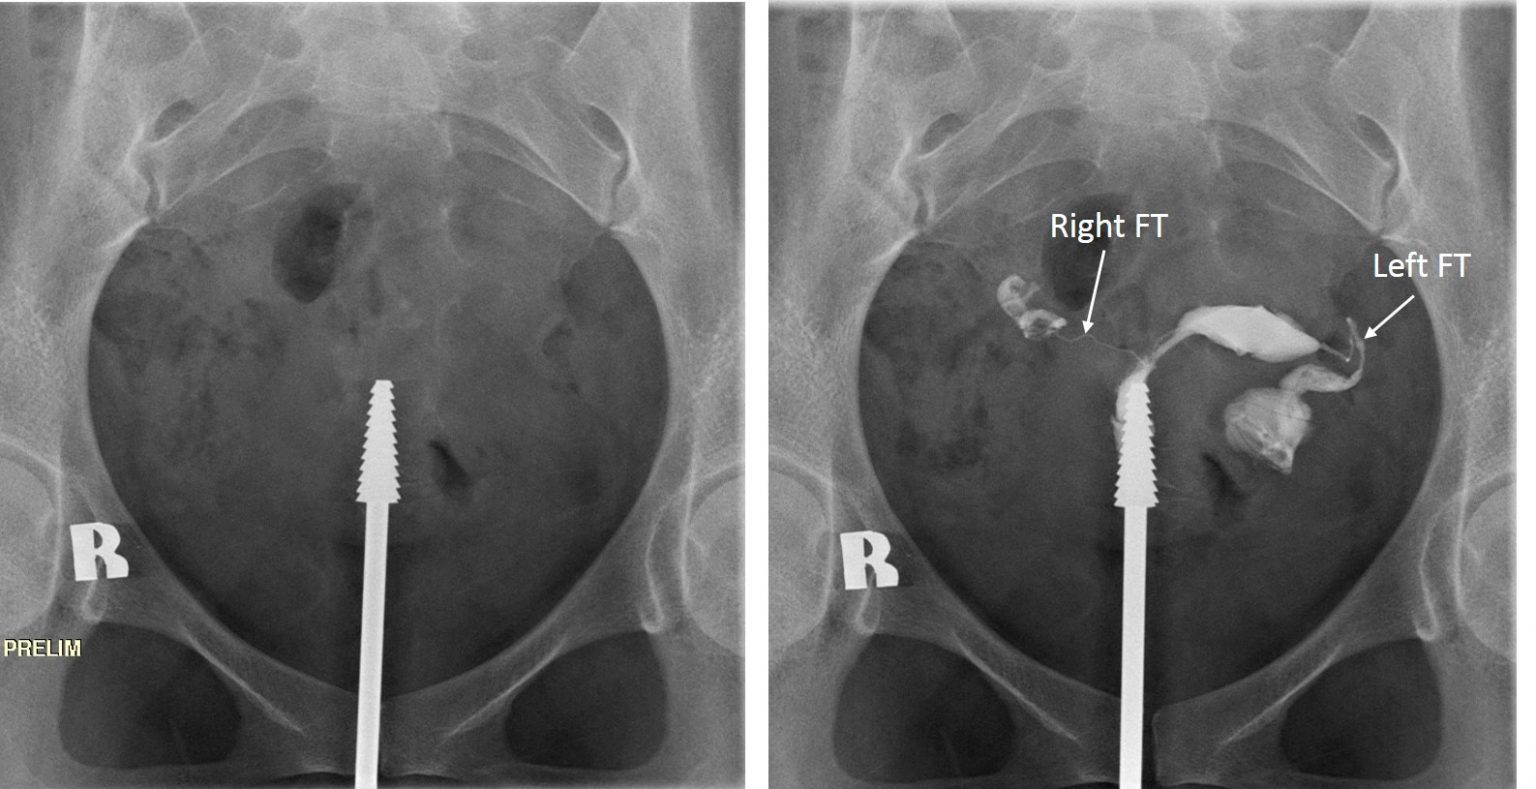

Peritubal adhesions on hysterosalpingogram Image

Peritubal adhesions on hysterosalpingogram Image Radiology Imaging Hysterosalpingogram Formed after the injection of a contrast material. Hysterosalpingogram (hsg) is an imaging procedure in which contrast dye is injected into the uterine cavity, progresses into. The technical quality of the hysterosalpingogram is important to limit factors leading to misinterpretations. It is also essential for the radiologist to be familiar with the normal and. Hysterosalpingography (hsg) has become a commonly. Radiology Imaging Hysterosalpingogram.